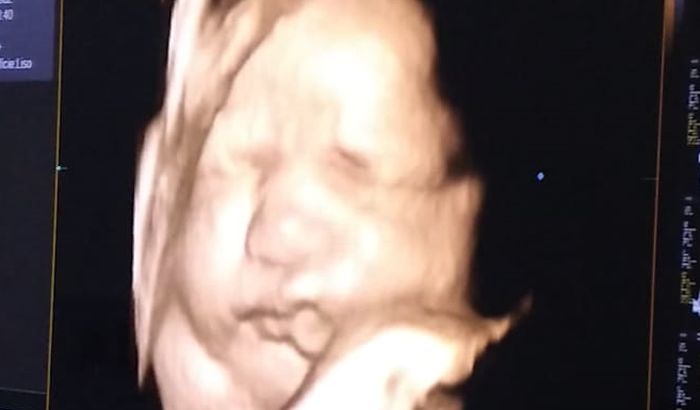

Olá Pessoal! Muitos de vocês perguntam o que dar pra Maria Clara de presente, quando ela vai chegar, entre outras coisas. Como chegamos aos 9 meses, nossa prioridade no momento é o nascimento dela (parto). Tentamos nos programar de diversas formas durante esses meses pra que nessa fase já estivesse tudo ok. Porém muitos contratempos aconteceram, o plano não cobre o parto, então decidimos abrir esse espaço pra quem desejar nos abençoar nessa reta final.

Estamos muito felizes e na expectativa para esse momento. Sabemos que vocês nos acompanham e torcem muito por essa chegada também. Desde já agradecemos todo carinho por nossa família e o investimento.